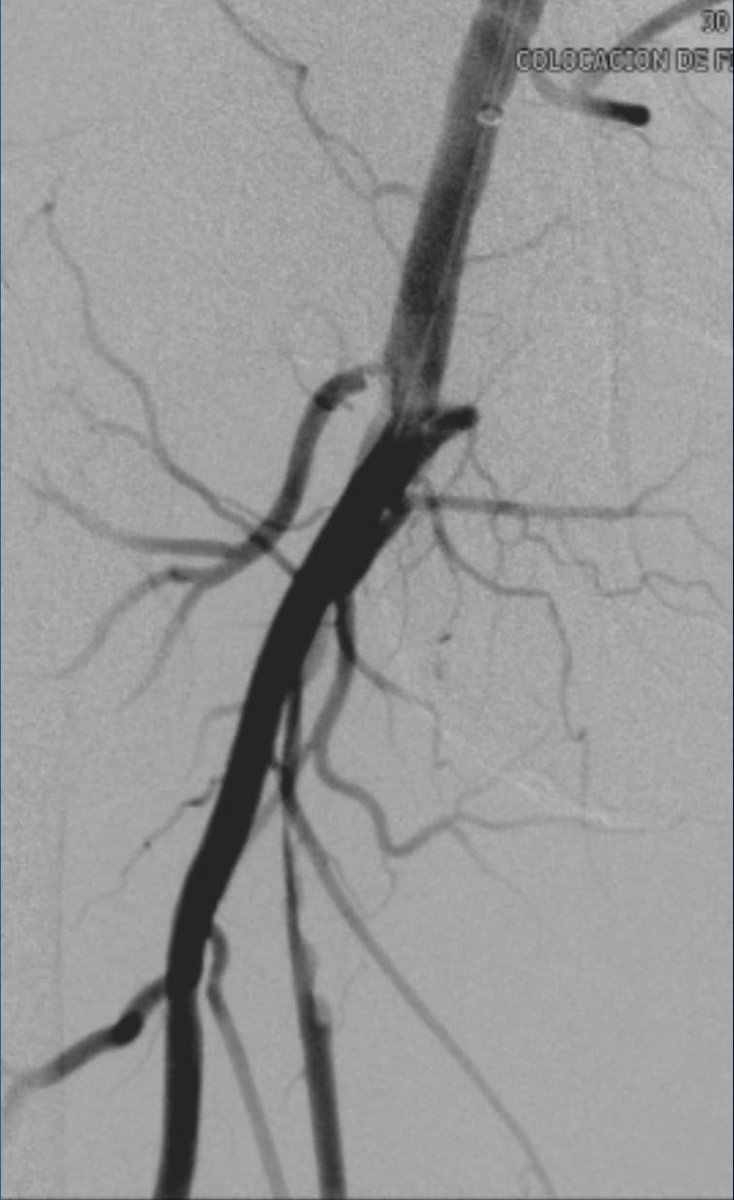

A patient with IVC atresia rolled into my office in a wheelchair. No options were offered for years. Successful IVC reconstruction. One week later, walked into my office for followup! One month later, living his best life, no pain and no limitations. #chogazi #irad #vascular #cardiotwitter @SIRRFS @SIR_ECS @SIRspecialists @VascularSVS @farkomd @AmputationSuck @ChengaziMD